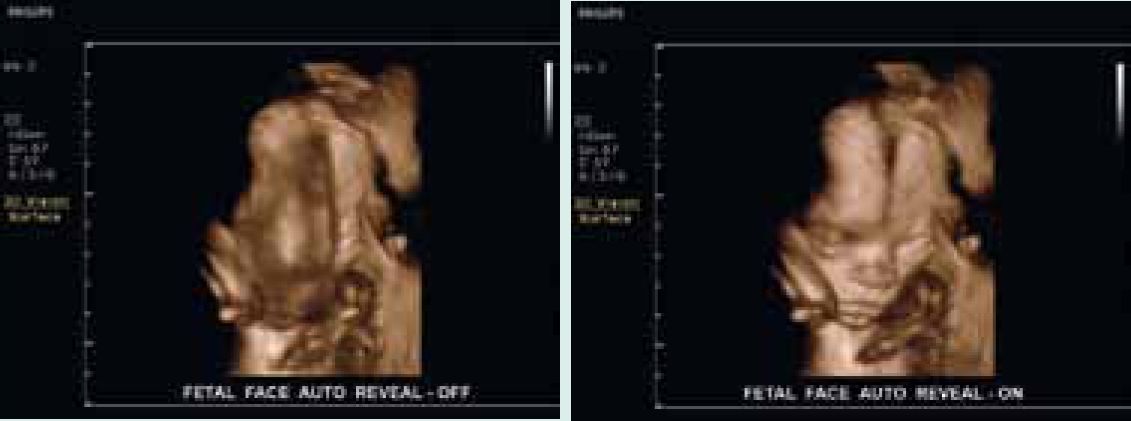

В фирменной функции автоматического воспроизведения лица используется метод автоматической сегментации, позволяющий «удалять» из объема 3D/4D-данных лишние ткани и шум перед лицом плода путем определения сферы расположения черепа.

Автоматическое воспроизведение лица

Захват 3D-изображения лица плода для выявления возможных дефектов и сокращения времени исследования в режиме 3D/4D.

Средства сегментации для автоматического воспроизведения лица |

Воспроизведение лица плода с помощью «удаления» лежащих перед ним тканей с изображения. Сокращение времени исследования и оптимизация работы одним нажатием кнопки. |